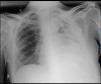

Paciente de 56 años que ingresó en la unidad de cuidados intensivos por neumonía grave de la comunidad complicada con empiema polimicrobiano por Streptococcus pneumoniae y Serratia marcescens (fig. 1). Evolucionó a shock séptico con disfunción multiorgánica y falleció. En la tomografía computarizada (TC) de tórax realizada, se objetivaba desestructuración del lóbulo superior izquierdo con importante hipoperfusión del parénquima, con esfacelos, cavidades necrosadas y niveles hidroaéreos en relación con neumonía necrosante (figs. 2 y 3). Este caso pone de manifiesto que aunque la radiología simple de tórax es la prueba inicial de imagen para evaluar una neumonía, la TC se debe de realizar siempre ante la existencia o sospecha de cualquier complicación de la misma, lo cual puede modificar el tratamiento y pronóstico.